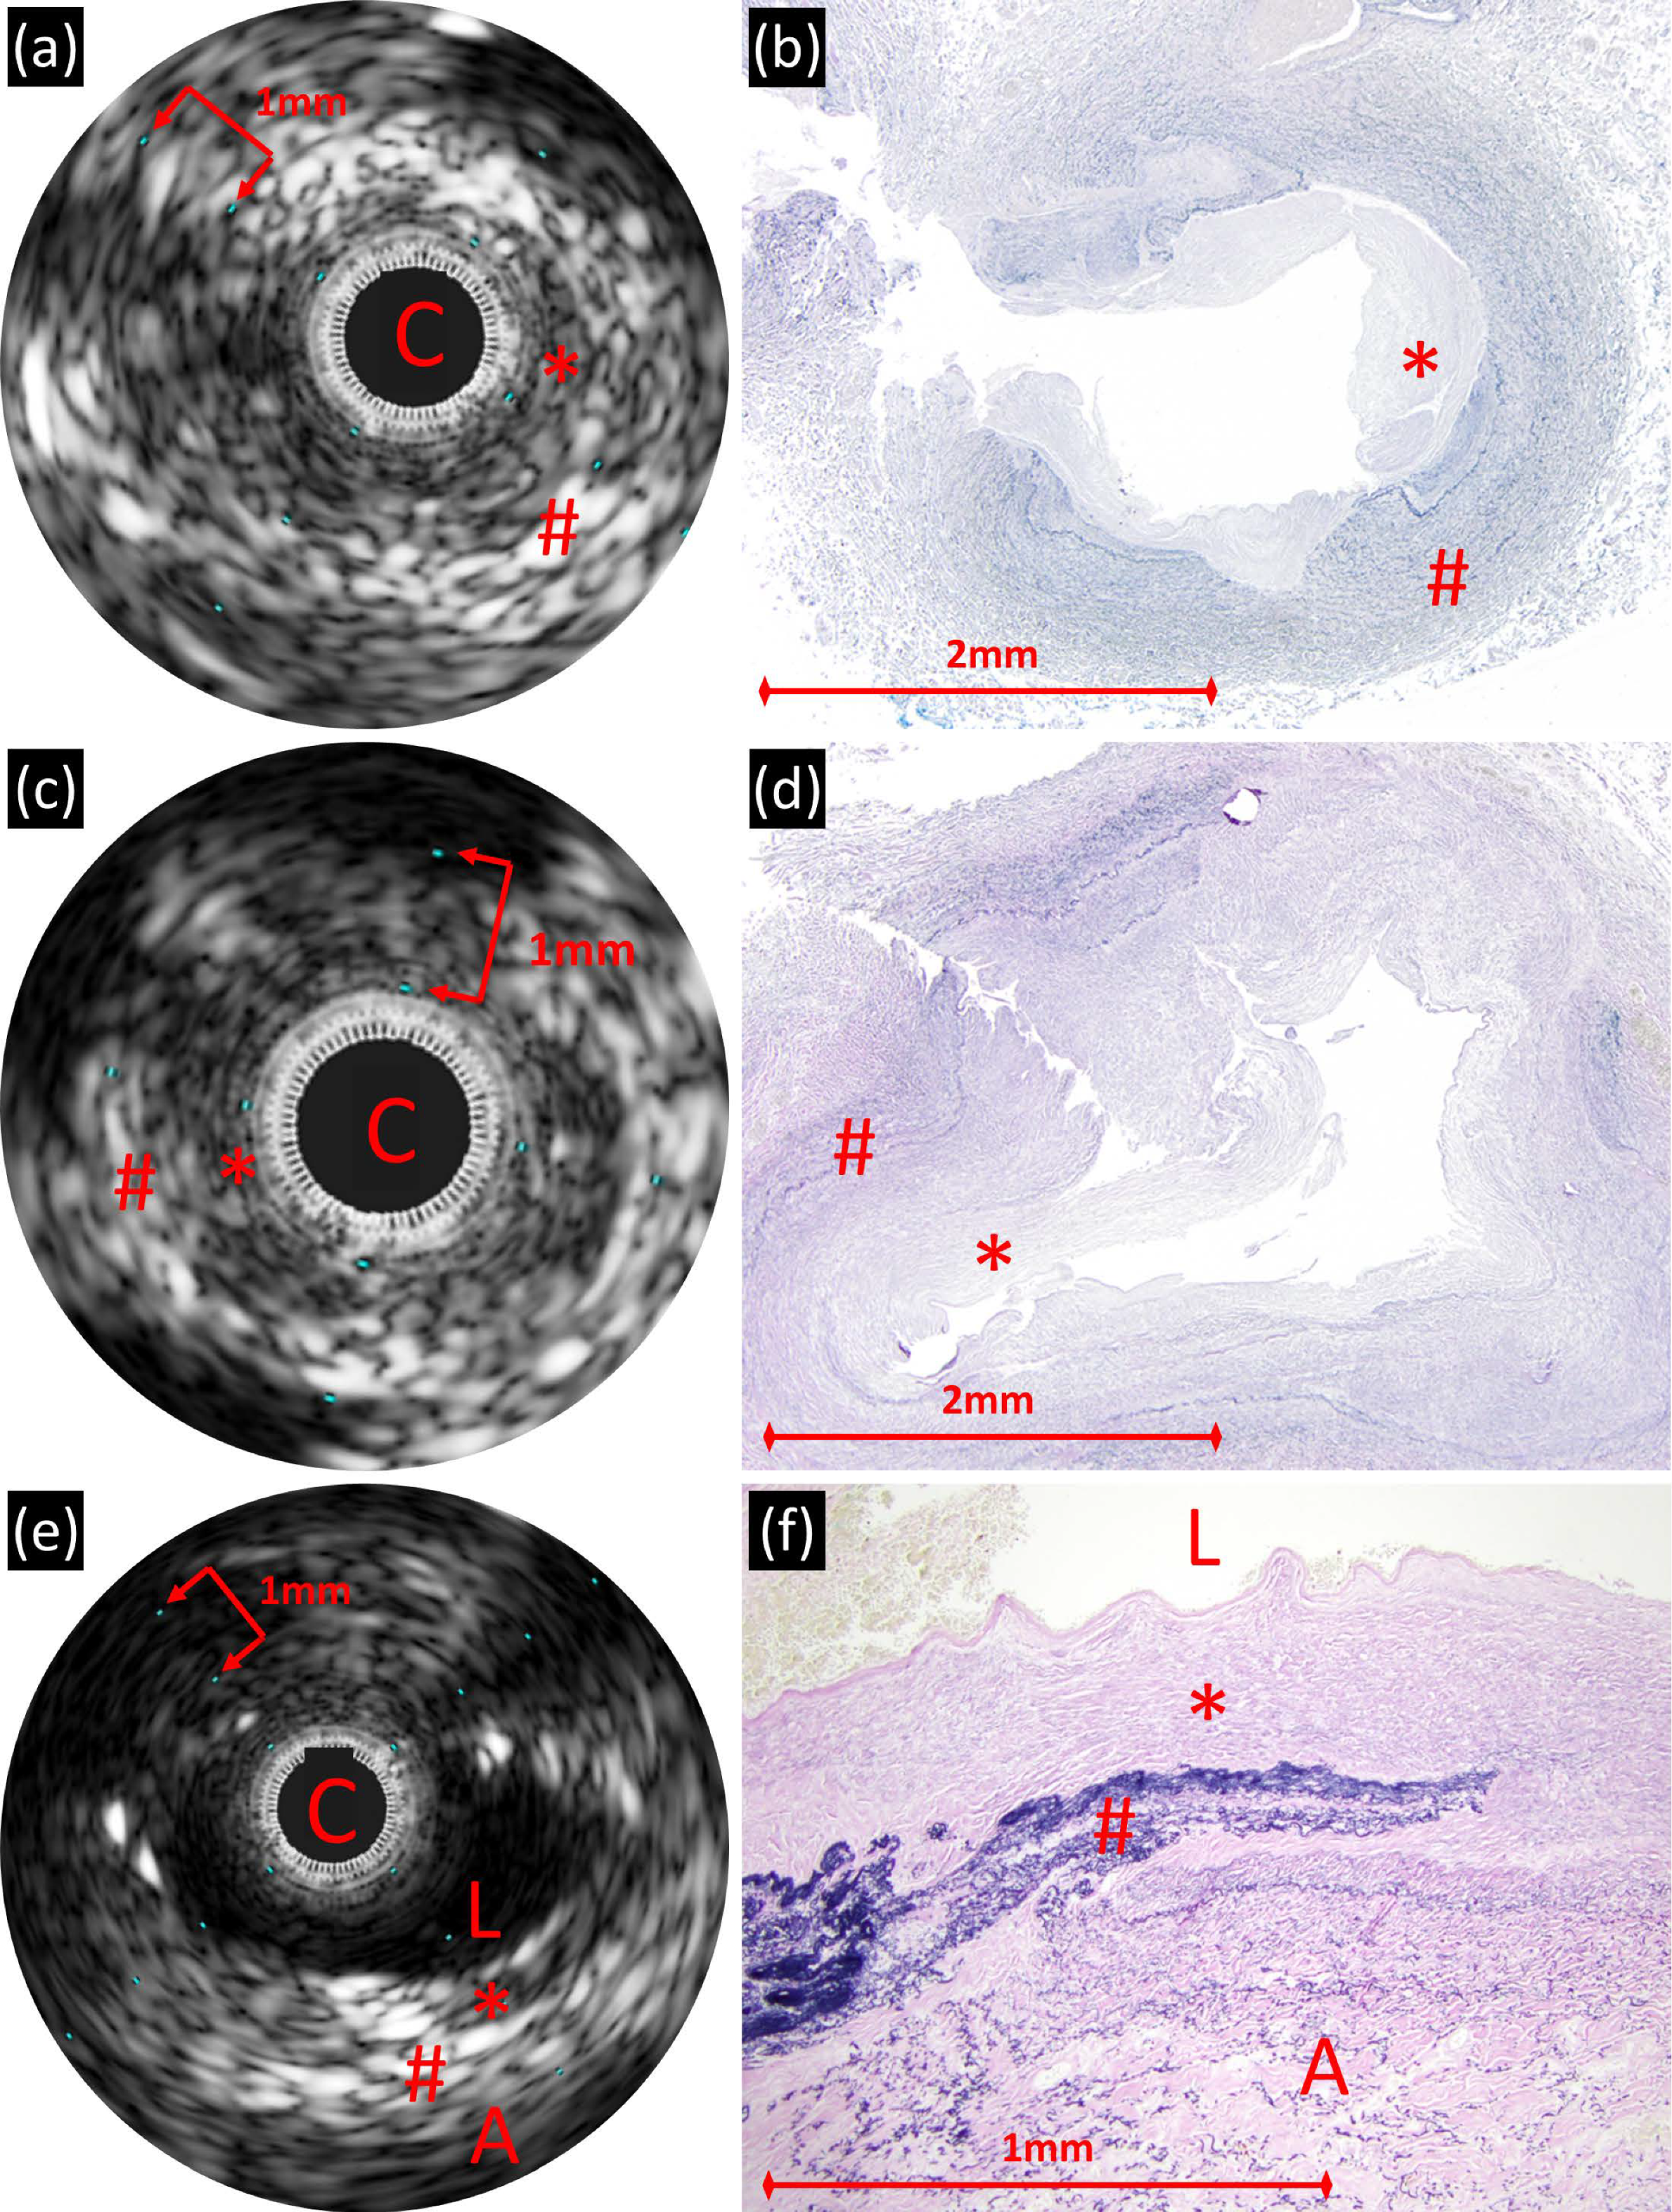

3.2.1. Postmortem PVS Veins

3.2.2. In Vivo PVS Veins

3.2.3. Control Veins

3.4. IVUS/Histology Correlation

3.4.1. Postmortem PVS Veins

3.4.2. In Vivo PVS Veins

3.4.3. Control Veins